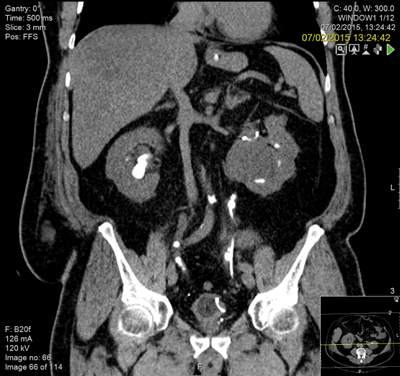

A 57-year-old male was transferred from a referring hospital with deteriorating renal function (creatinine 830). He had a laparostomy secondary to ischaemic colitis and a partial right staghorn calculus, bilateral ureteric stones and numerous stones within his left kidney. He was obese, diabetic and had a previous myocardial infarction with a right-sided stoma and an open abdominal wound, secondary to a hemi-colectomy.

Following resuscitation with a right nephrostomy, he underwent bilateral ureteroscopy and was left with bilateral stents and small fragments adjacent to the ureteric stent.